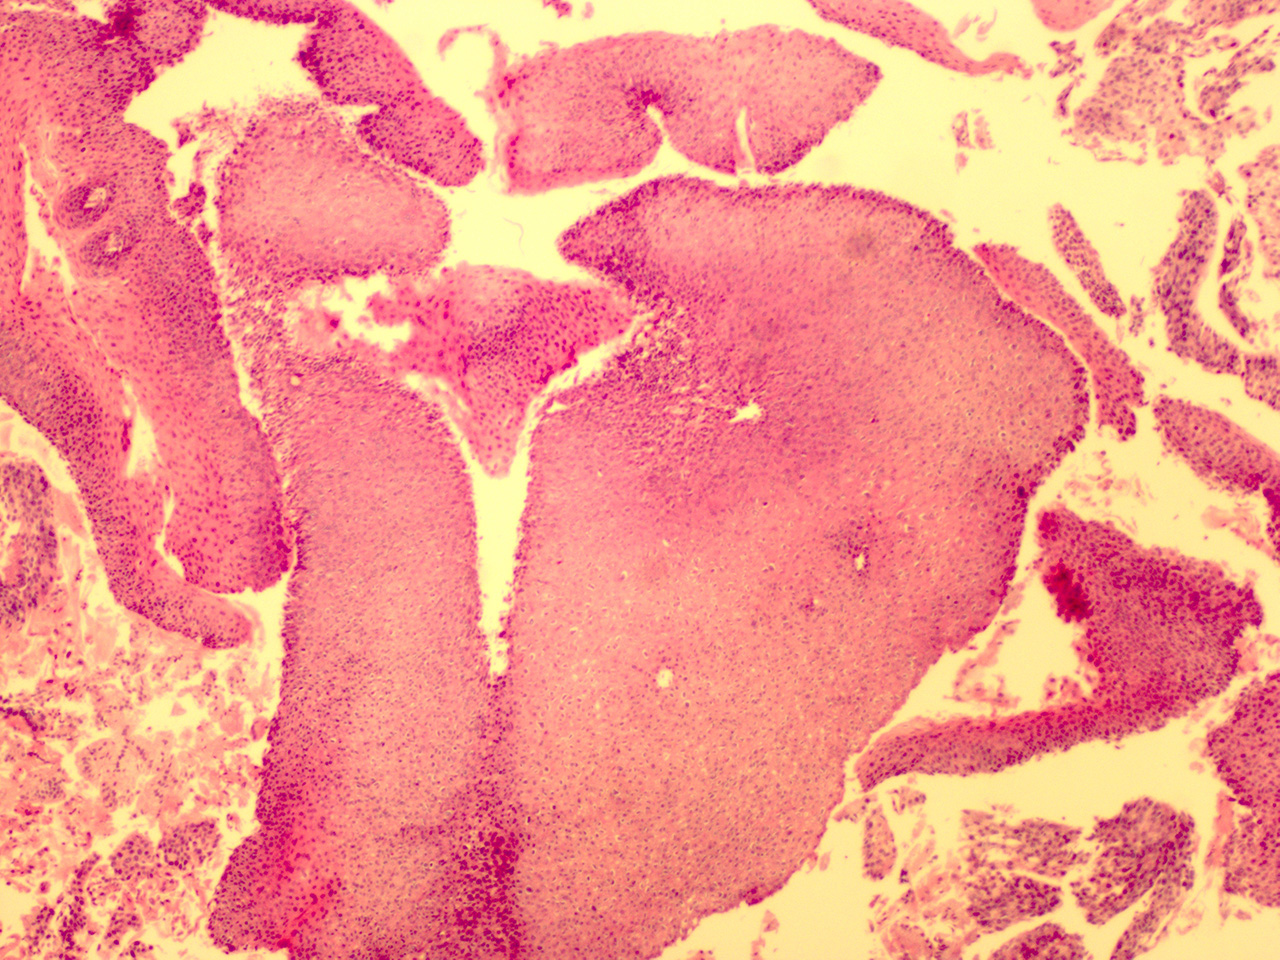

![]() Case 4

Soft Bx CIN 3

10x - Low Power |

Case 4

40x - High Power |